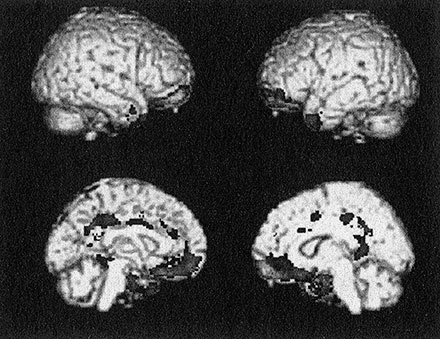

Если сканы мозга заключенных подростков покажут те же результаты, что и у взрослых, это позволило бы предположить, что открытая нами атрофия едва ли происходит из-за того, что эти участки мозга не используются. Самым простым и очевидным выводом был бы тот, что атрофия паралимбической системы присутствует у них с рождения. Он соответствовал принципу бритвы Оккама – требовал меньше всего допущений.

Рис. 9. Результаты первого анализа структурной МРТ заключенных подростков, собранные при помощи мобильного томографа (четыре изображения слева). Затененные области соответствуют участкам мозга, атрофированным у подростков с чертами бессердечия и без-различия. Данные по взрослым заключенным мужского пола при-ведены справа для сравнения. Результаты обеих групп поразительно похожи. В обеих группах большая часть паралимбической системы показывает сниженную плотность серого вещества, то есть атрофию. Данные по подросткам взяты из Ermer E. et al (2013). Aberrant paralimbic gray matter in incarcerated male adolescents with psychopathic traits // Journal of the American Academy of Child and Adolescent Psychiatry, 52, 94–103. Данные по взрослым из Ermer E. et al (2012). Aberrant paralimbic gray matter in criminal psychopathy // Journal of Abnormal Psychology, 121(3), 649–658

Результаты меня снова поразили (см. рис. 9). У заключенных подростков с чертами бессердечия и безразличия по баллам ППЧ для детей и подростков были те же аномалии мозга, что и у взрослых психопатов. Снимки мозга у тех и других оказались похожи до жути.

Я испытывал смешанные чувства. Как ученый я ощущал волнение и радость оттого, что моя гипотеза подтвердилась. Как человек я жалел этих молодых людей с аномалией мозга. Было такое чувство, будто моя лаборатория открыла новую болезнь, от которой не было лекарств.

Но результаты были достоверные. Нас никто не мог упрекнуть в том, что мы опубликовали небольшую выборку {91}. В нашем исследовании участвовало в десять раз больше подростков, чем у ближайшего конкурента.